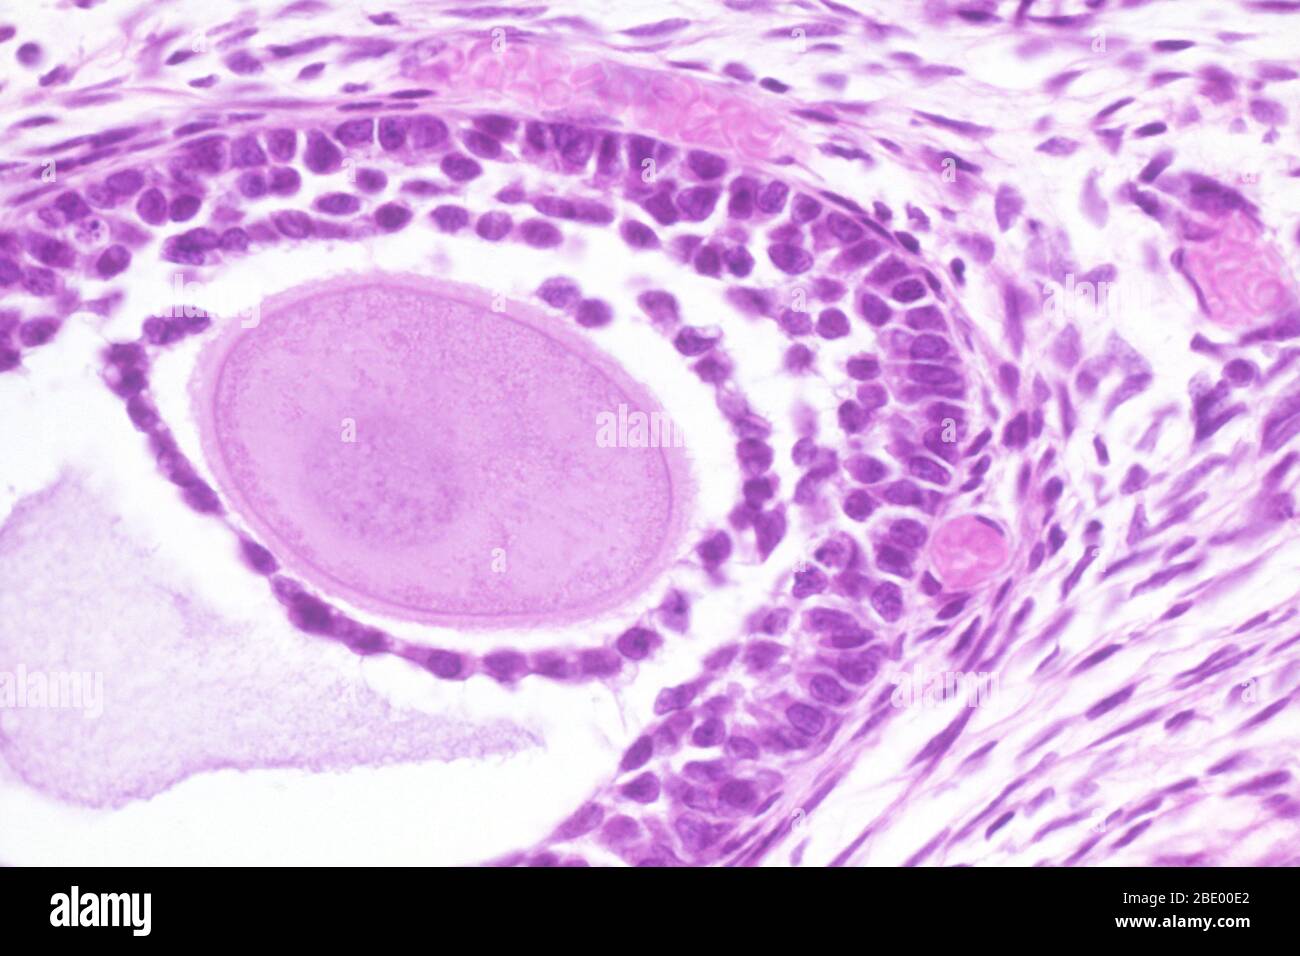

Eierstock Der Katze

Dieses Bild kann kleinere Mängel aufweisen, da es sich um ein historisches Bild oder ein Reportagebild handel